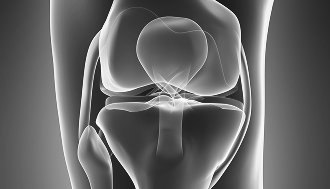

인공관절치환술

기능 회복

통증 완화